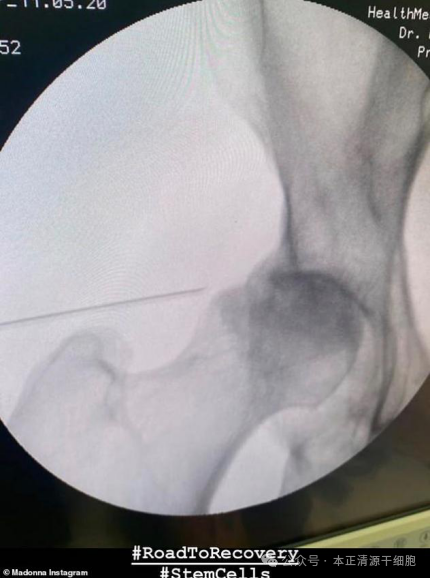

2020年5月15日,英国《每日邮报》在线刊登报道,麦当娜因其在《X夫人》的欧美巡演中膝盖受伤接受了干细胞治疗,随后包括BBC旗下的《音乐-新闻台》在内的众多媒体纷纷对此进行了报道

上图:媒体报道麦当娜发布的X光片

下图:下肢骨关节立体图